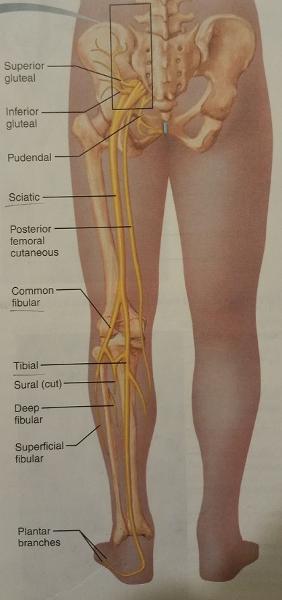

The sacral plexus arises from the ventral rami of which lumbar and sacral nerves?

L4-S4

1. The nerves of the sacral plexus supply which 2 body parts?

2. The nerves of the sacral plexus also supply which 2 groups of fibers of which 2 body parts?

1. The sacral plexus nerves supply...

- buttock

- posterior surface of the thigh

2. The nerves of the sacral plexus also supply...

- sensory fibers of the leg and foot

- motor fibers of the leg and foot

What is the major peripheral nerve of the sacral plexus?

Sciatic nerve

The sciatic nerve arises from the ventral rami of what lumbar and sacral nerves?

L4-L5 and S1-S3

What is the largest nerve in the body?

Sciatic nerve

The sciatic nerve serves which group of muscles of which body part and also, which general feature of that body part?

Serves the flexor muscles of the posterior thigh and the skin of the posterior thigh

In the popliteal region, the sciatic nerve divides into which 2 nerves?

1. common fibular nerve

2. tibial nerve

The common fibular nerve and the tibial nerve supply the muscles of which body part, and what general feature of that body part?

Supply the leg muscles and the skin of the leg

1. Give an example of a muscle served by the common fibular nerve.

2. Give an example of a muscle served by the tibial nerve.

1. Extensor digitorum longus

2. Flexor digitorum longus

The common fibular nerve arises from the ventral rami of what lumbar and sacral nerves?

L4-S2

The tibial nerve arises from the ventral rami of what lumbar and sacral nerves?

L4-S3